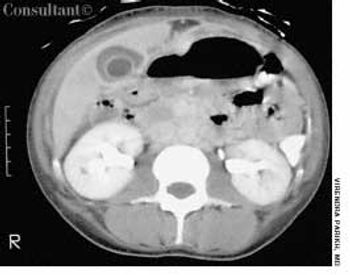

A 13-year-old girl who had leukemia presented to the emergency department with fever; chills; weight loss; fatigue; and a painful, erythematous rash with a central black lesion on the upper thigh. The patient was neutropenic and had been undergoing chemotherapy for 1 week.